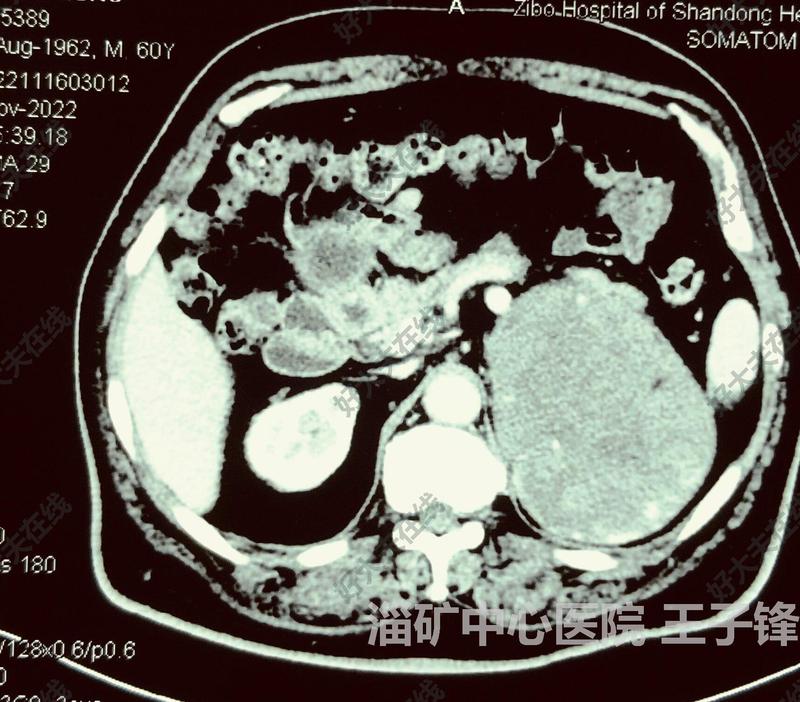

治療前 患者男,61歲,左側(cè)腎上腺巨大腫瘤,瘤體約12cm,因瘤體大,術(shù)前考慮皮質(zhì)癌及嗜鉻細(xì)胞瘤均不排除,目前患者腦出血3個(gè)月,口服酚卞明1月 治療中 行腹腔鏡下左腎上腺腫瘤切除(經(jīng)腹),瘤體大,瘤體表面血供豐富 治療后 治療后7天 術(shù)后病人恢復(fù)好,術(shù)后病理為左腎上腺血管瘤。